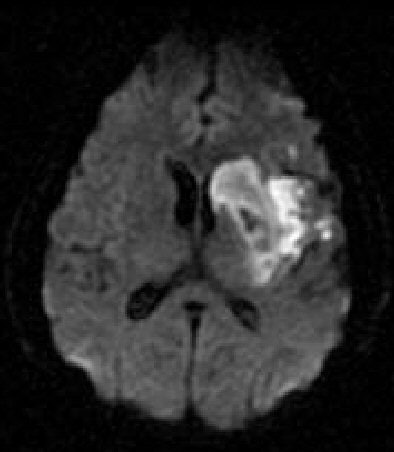

![]() |

| Diffusion-weighted MRI obtained immediately after perfusion CT demonstrates only a slightly hyperintense region in the left basal ganglia. Images courtesy of Dr. Sotirios Bisdas. |